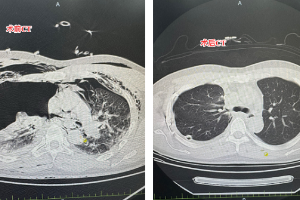

被“忽略”的身体警报:一次心肺运动试验,揪出胸痛背后的“真凶”

故事始于一名中年男性患者,他来到玉溪市人民医院心内科,向医生讲述:他总感觉胸口像压了一块石头,隐隐作痛持续一周,这感觉虽不剧烈,却持续困扰着他,让人不安。患者无高血压、糖尿病等病史,平素体检也未见明显异常。然而,对于一位体型偏胖(BMI 24.8kg/m²)、有十余年吸烟史的中年男性而言,心血管疾病的风险不容忽视。接诊医生在详细问诊和体格检查后,为他启动了一套严谨的排查流程。